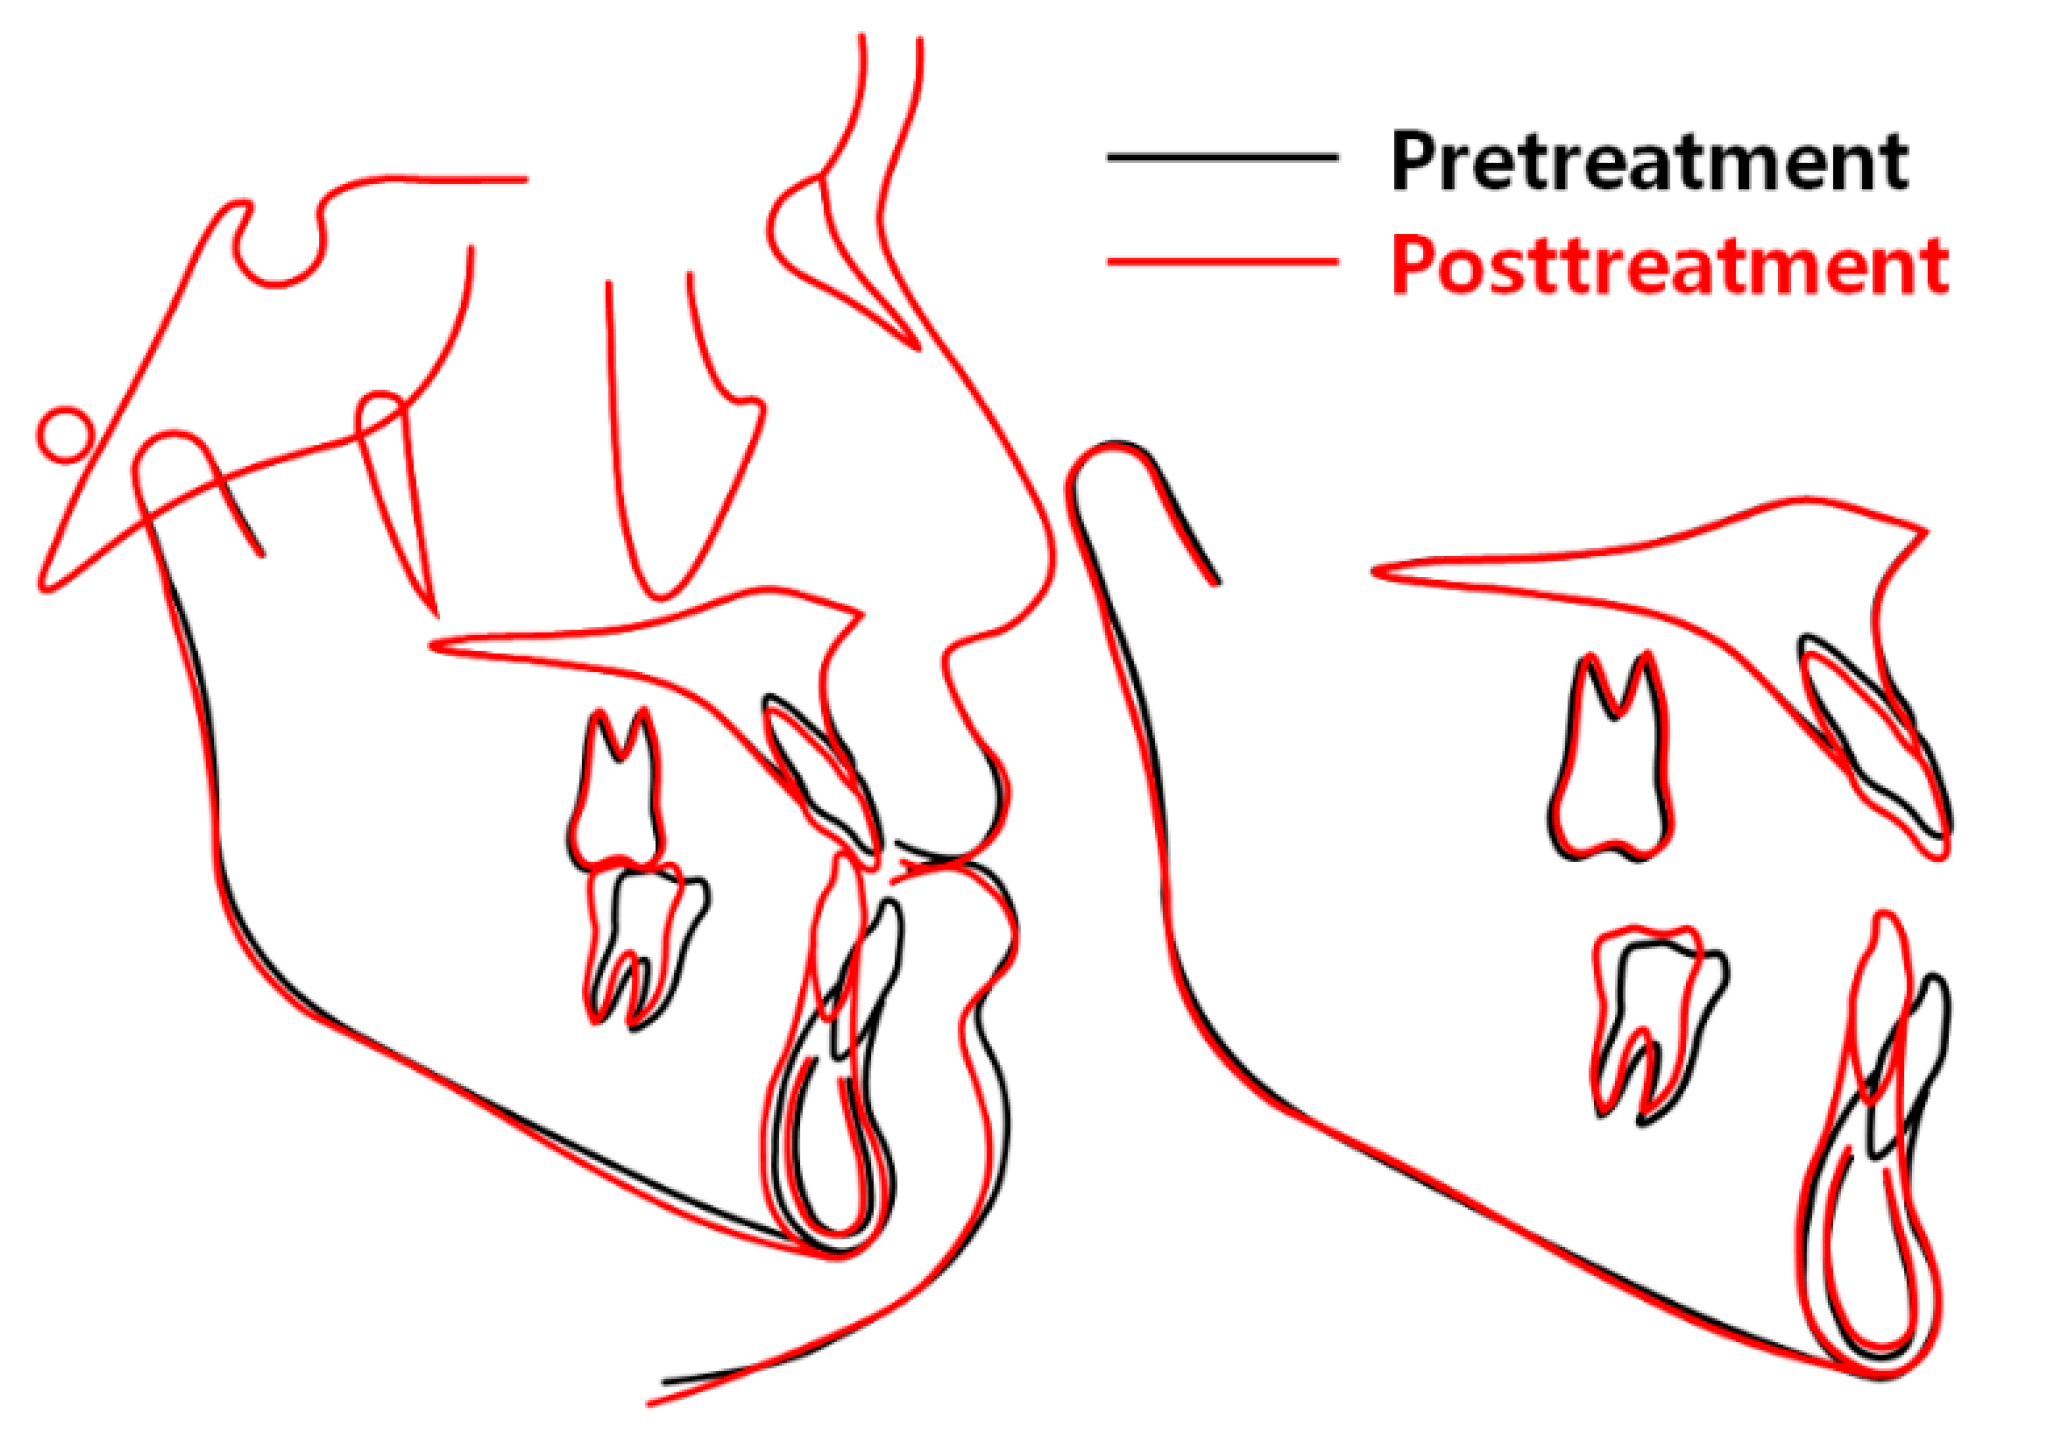

2.5. Treatment Results